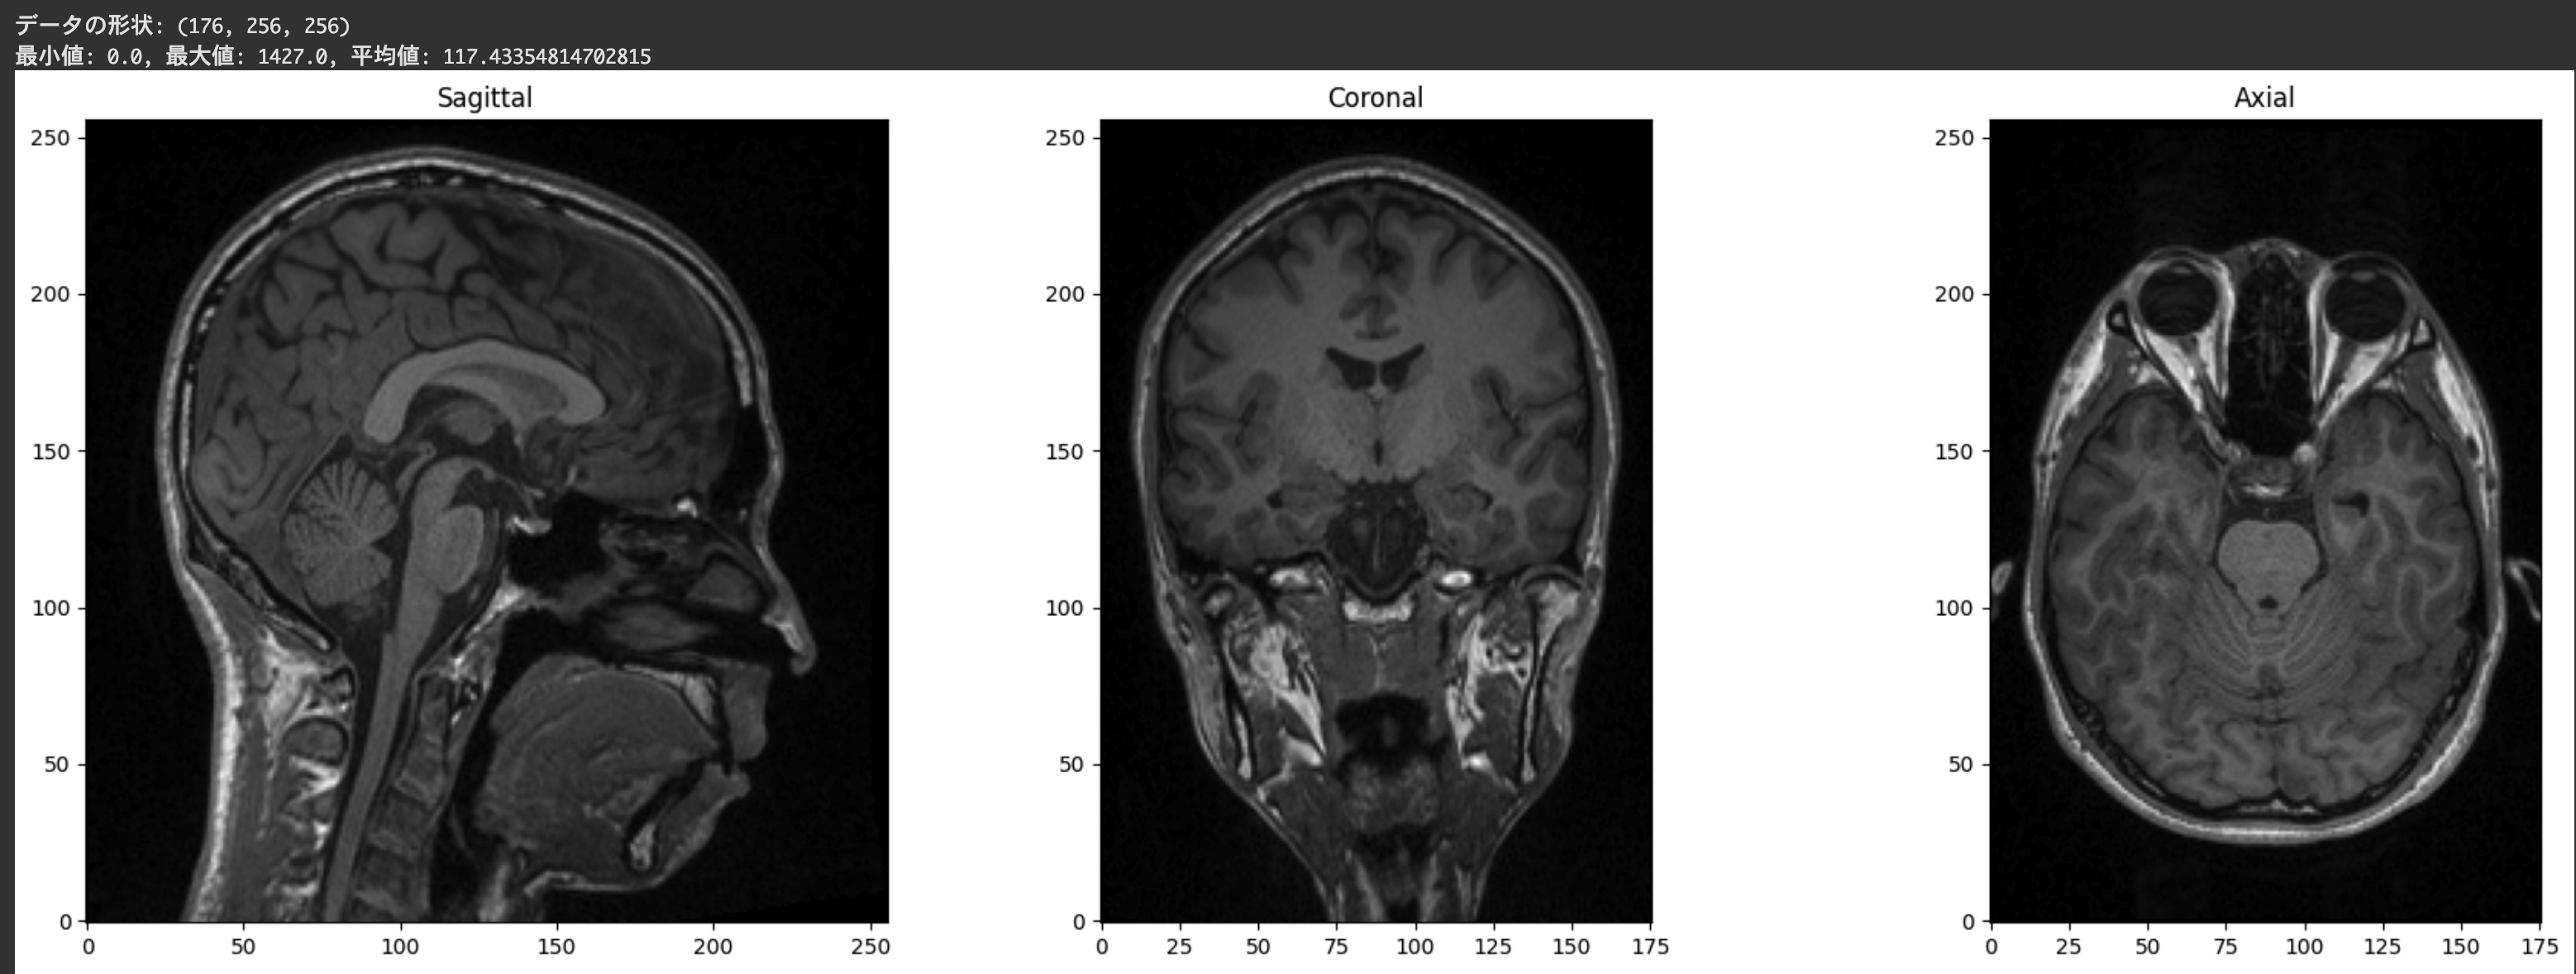

画像データの取得と表示

NiBabelで読み込んだ画像データは、NumPy配列として取得できます。これにより、様々な数値処理や可視化が可能になります。NumPy配列にするにはget_fdata属性を用います。

# 画像データをNumPy配列として取得

data = img.get_fdata()

print(f"データの形状: {data.shape}")

print(f"最小値: {data.min()}, 最大値: {data.max()}, 平均値: {data.mean()}")

# 3次元データ(x, y, z)の中央のスライスを取得

x, y, z = data.shape

slice_x = data[x//2, :, :] # 矢状断面(Sagittal)

slice_y = data[:, y//2, :] # 冠状断面(Coronal)

slice_z = data[:, :, z//2] # 軸位断面(Axial)

# Matplotlibを使用して3つの断面を同時に表示

plt.figure(figsize=(18, 6))

plt.subplot(131)

plt.imshow(slice_x.T, cmap='gray', origin='lower')

plt.title('Sagittal')

plt.subplot(132)

plt.imshow(slice_y.T, cmap='gray', origin='lower')

plt.title('Coronal')

plt.subplot(133)

plt.imshow(slice_z.T, cmap='gray', origin='lower')

plt.title('Axial')

plt.tight_layout()

plt.show()